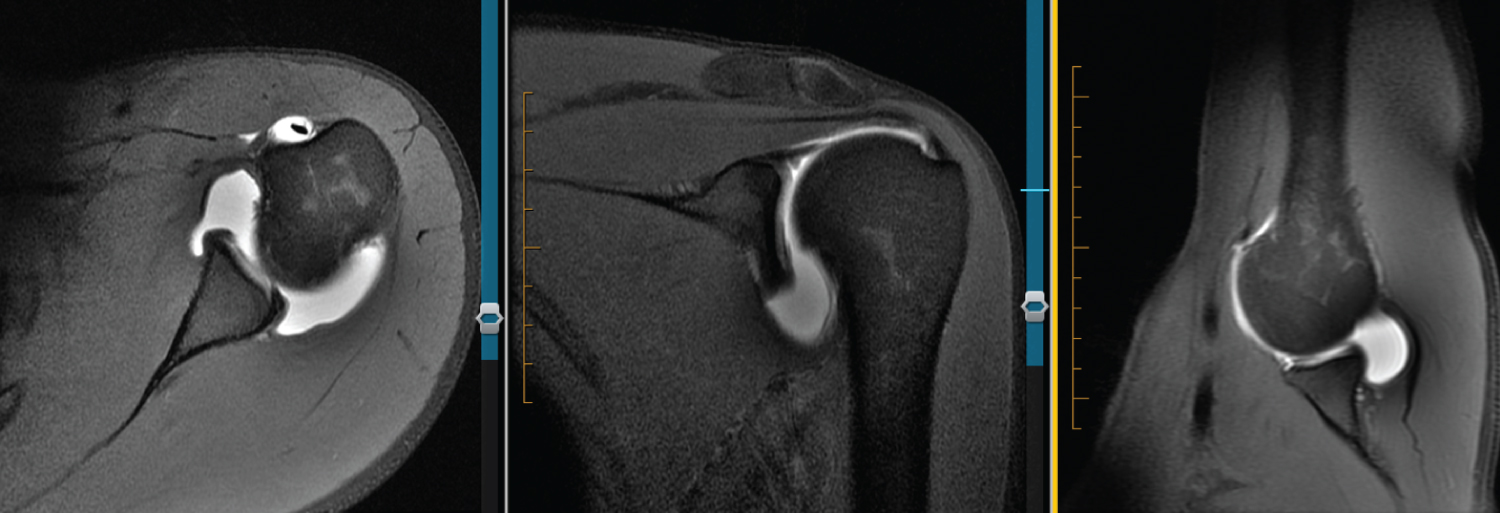

Figure 10: 28 F R MRA. Axial view shows blunting of anteroinferior labrum compared with posterior triangular appearance. ABER view appears normal. Also appears to be anterosuperior labral tear on coronal. View Figure 10

Figure 11: 28 F L MRA. Axial view shows blunting, rounding of anteroinferior labrum with undefined features. ABER view shows possible splitting of labrum. Anterosuperior labral tear visualized coronal. Arthroscopically -labrum and capsule were shifted medially and appeared to have a plastic deformation to them. There was no detachment or tearing of the periosteum, at most the capsule was patulous along with laxity to the IGHL but once again no tearing of any of the structures at the anteroinferior labra. Thus, no process of healing could occur (fibrosis, or scarring as seen in ALPSA). View Figure 11